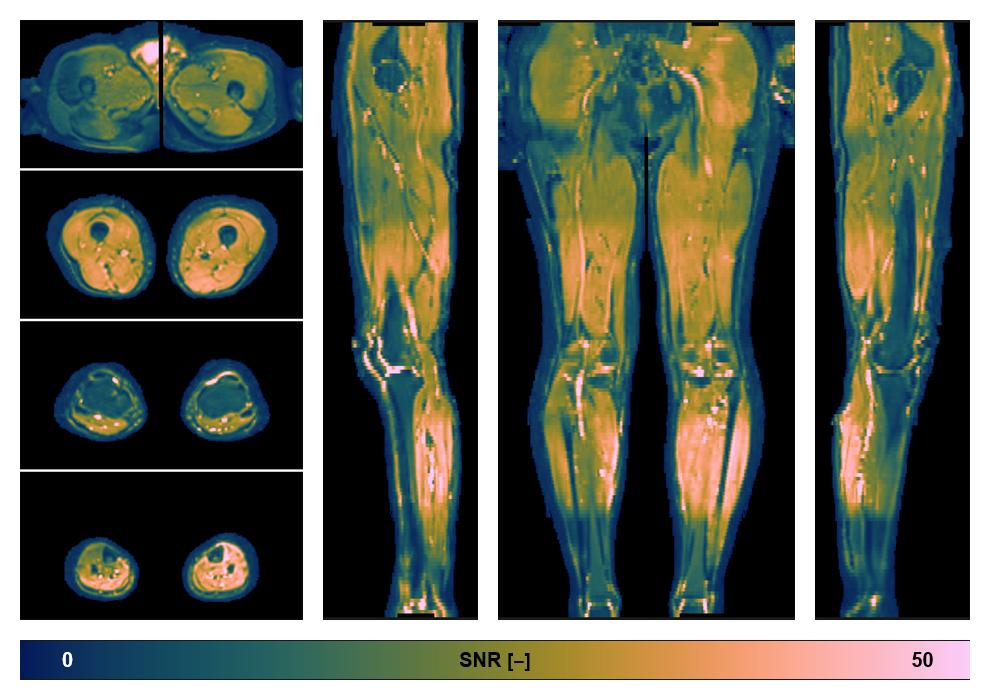

• SNR distribution

The SNR distribution of the dixon data.